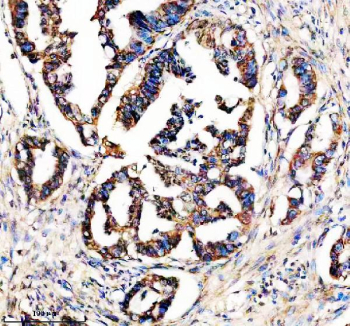

Immunohistochemical staining of STX4 using anti-STX4 antibody. STX4 was detected in a paraffin-embedded section of human colon cancer tissue. Heat mediated antigen retrieval was performed in EDTA buffer (pH 8.0, epitope retrieval solution). The tissue section was blocked with 10% goat serum. The tissue section was then incubated with 2 ug/ml rabbit anti-STX4 antibody overnight at 4oC. Peroxidase Conjugated Goat Anti-rabbit IgG was used as secondary antibody and incubated for 30 minutes at 37oC. The tissue section was developed using an HRP secondary and DAB substrate.